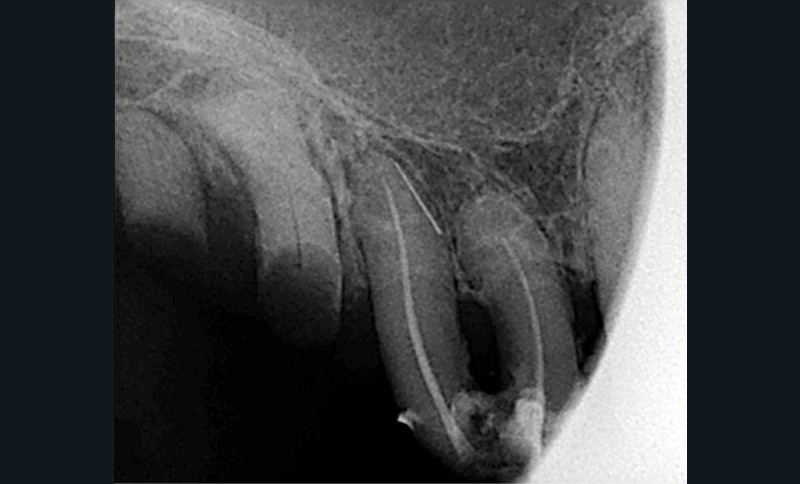

À la mandibule, nous notons que :

– les dents 45, 46, et 47 sont absentes ;

– la dent 37 est liée à 36 par un jonc retenu dans un composite et présente une image apicale et une alvéolyse distale dépassant le tiers de la racine. L’édentement n’a jamais été compensé.